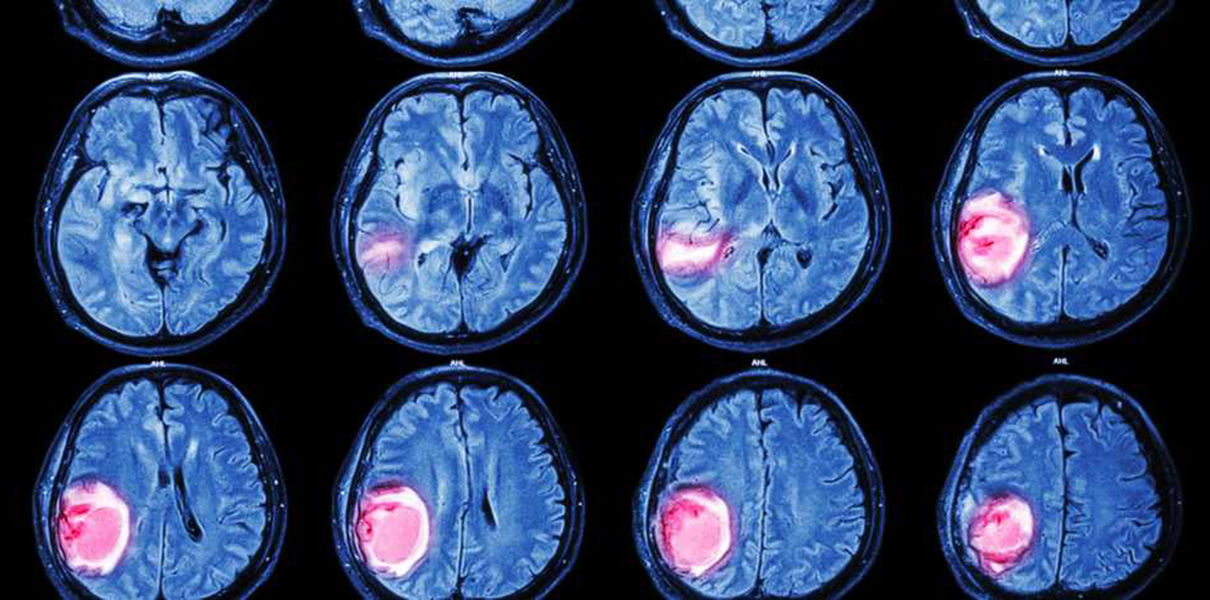

Рак мозга – злокачественная опухоль в области головного мозга. Различают около 130 видов опухолей данного органа. Одной из причин заболевания может быть стресс и недосыпание.

Развитие рака головного мозга может быть обусловлено разнообразными причинами: наследственность, радиоактивное облучение, токсическое воздействие ртути или свинца, травмы головы, вредные привычки, повышенное артериальное давление, частые или сильные стрессы, недосыпание и постоянное переутомление.

Чаще всего опухоли головного мозга диагностируют у людей старше 45-50 лет.